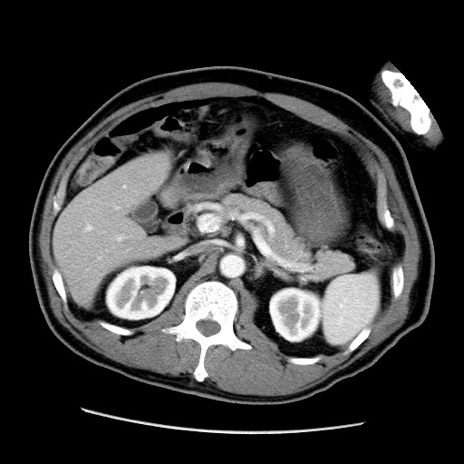

症例22(横断像)

【症例】50歳代男性

【主訴】腹痛

【現病歴】AVMからの被殻出血のため回復期リハ病棟入院中。 本日午後3時頃急に下腹部痛が出現した。

【既往歴】AVM、被殻出血、虫垂炎、高血圧

【身体所見】意識晴明、左半身不全麻痺、会話の理解は良好、36.5°C、腹部:膨隆、全体に板状硬、下腹部正中に圧痛点あり、反跳痛-、筋性防御不明、右下腹部にope scar

【データ】WBC 9400、CRP 0.06